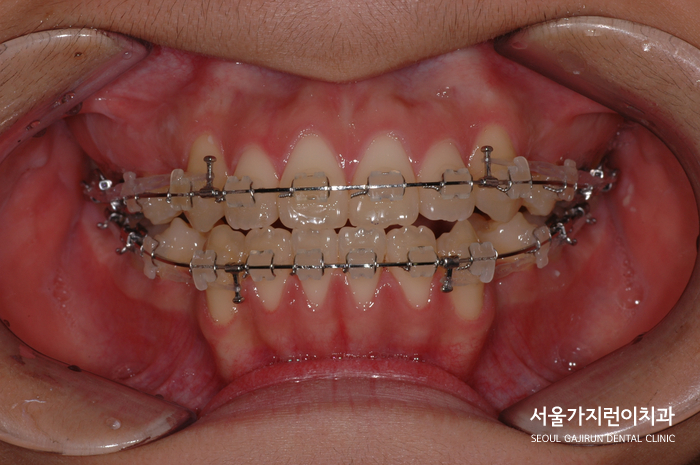

교정장치 부착 후 치아이동이 잘 되는 것을 확인했으며 점점 발음과 식사시 불편도 줄었다며 치료도중 만족감도 좋으신 편이었습니다. 게다가 치아가 가지런해지면서 얼굴 윤곽도 부드러워지고 인상이 한층 밝아져 자신감이 생긴 모습이셨는데요.

교정용 고무줄을 적절히 활용해서 치아이동을 진행했으며 이로 인해 돌출입증상도 완화된 것을 확인할 수 있었습니다. 기울어진 어금니는 바로 세워 교합을 완성했고 방향과 경사를 조금씩 바로 잡아 상하악 앞니를 서로 닿게 했는데요. 교정 이후 전체적인 치열도 가지런해진 것을 확인하여 심미성이 좋아진 사례입니다.